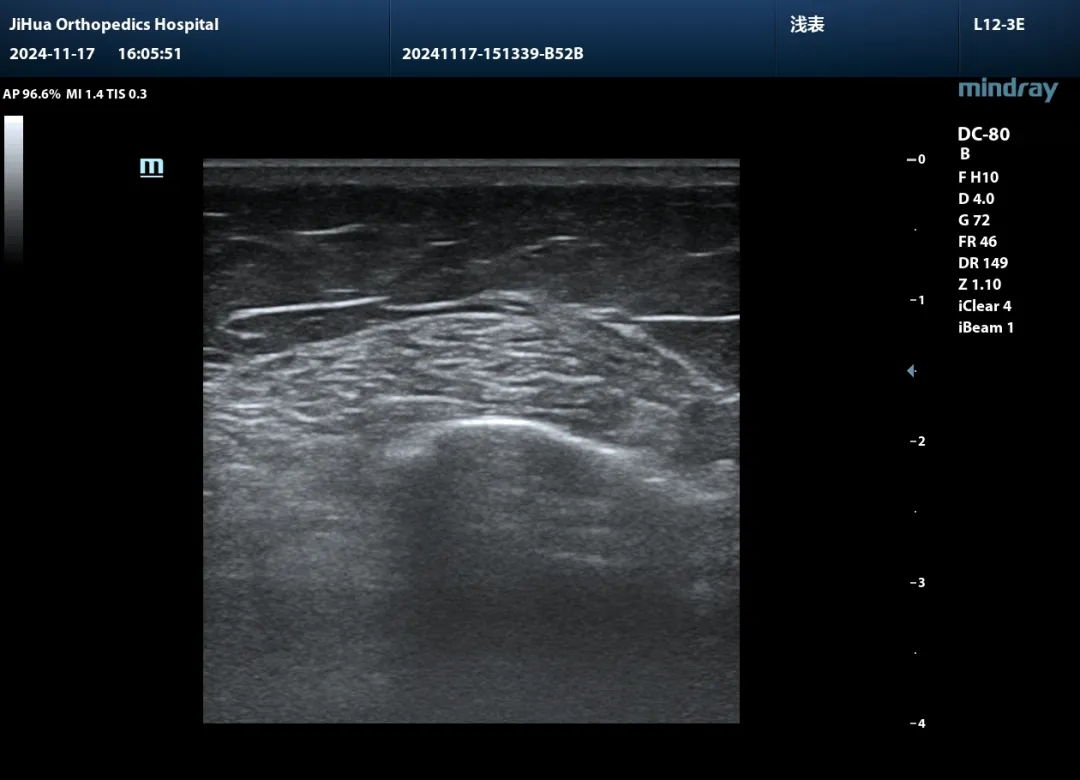

一旦体格检查发现异常,现场即可启动影像扫查,清晰呈现损伤程度、失稳根源与结构障碍。结合X线、CT、MRI等影像资料,精准的诊断思路豁然开朗。